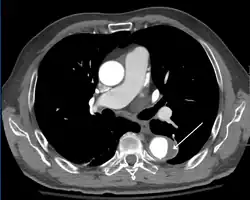

Computed tomography

Computed tomography angiography is a fast, non-invasive test that gives an accurate three-dimensional view of the aorta. These images are produced by taking rapid, thin-cut slices of the chest and abdomen, and combining them in the computer to create cross-sectional slices. To delineate the aorta to the accuracy necessary to make the proper diagnosis, an iodinated contrast material is injected into a peripheral vein. Contrast is injected and the scan performed using a bolus tracking method. This type of scan is timed to injection to capture the contrast as it enters the aorta. The scan then follows the contrast as it flows through the vessel. It has a sensitivity of 96 to 100% and a specificity of 96 to 100%. Disadvantages include the need for iodinated contrast material and the inability to diagnose the site of the intimal tear.

-

CT with contrast demonstrating aneurysmal dilation and a dissection of the ascending aorta (type A Stanford)

Chest CT with descending (type B Stanford) aortic dissection (red circle)

Type A dissection with pericardial effusion as a result.